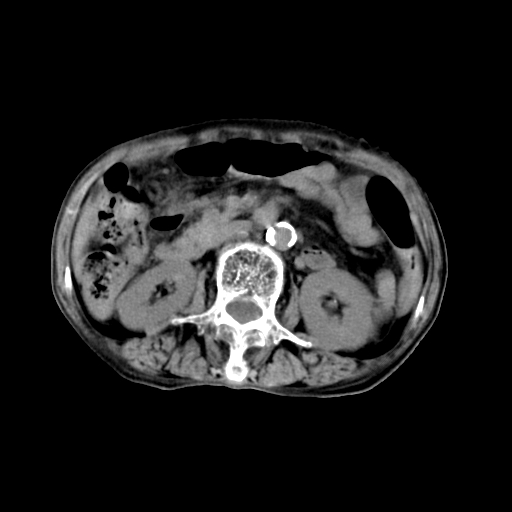

女,68岁,腹胀、恶心两周,先做ct平扫,当时家属不同意强化,6天后家属要求增强扫描。

考虑:胃窦ca,腹水,脂肪肝

1)胃窦壁厚,考虑胃窦癌?建议行胃镜检查。 2)局灶性脂肪肝。

不均匀脂肪肝,胃腔改变须结合钡餐或胃镜观察